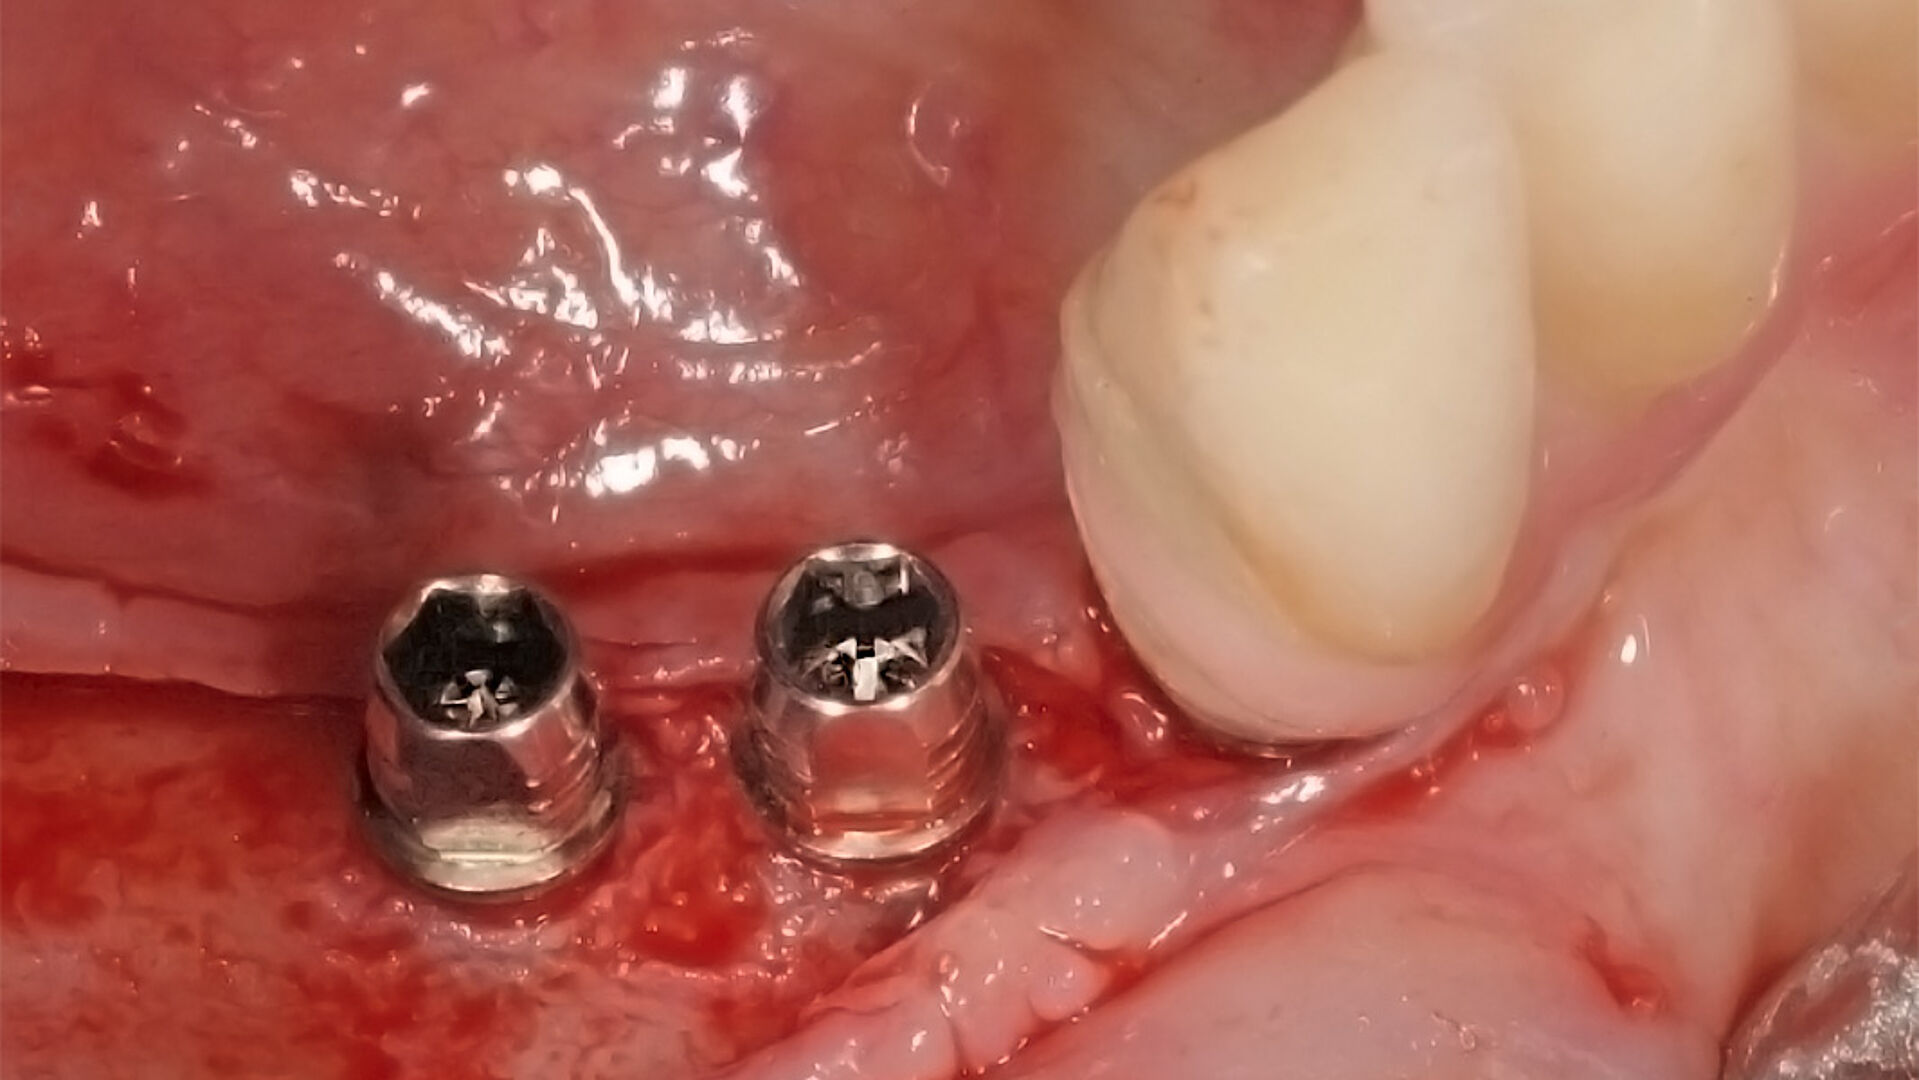

Die gedeckte Einheilung ist in manchen klinischen Situationen unabdingbar. Mit einem gestecktem Einbringpfosten, einer Metallverschlussschraube und einem Einpatienten-Formbohrer in einer Verpackung bleibt sich iSy auch mit seinem Konzept für die gedeckte Einheilung im Sinne der Effizienz treu. Dank des gesteckten Einbringpfostens entfällt auch hier nach der Implantatinsertion das Lösen einer Schraube.

Die transgingivale Einheilung dentaler Implantate ist ein wissenschaftlich gut untersuchtes und klinisch erfolgreiches Verfahren. Für die transgingivale Einheilung sollten die Implantate primärstabil inseriert werden, nur kleine Hartgewebeaugmentationen notwendig sein und ausreichend stabiles Weichgewebe vorliegen. Um in Fällen mit Augmentationsbedarf das iSy Implantatsystem verwenden zu können – ohne die Implantatbasis demontieren zu müssen – bietet das iSy System Implantate mit gestecktem Einbringpfosten an. Nach gedeckter Einheilung und Freilegung des Implantats können drei verschieden breite Gingivaformer eingebracht und im Anschluss sowohl eine digitale als auch konventionelle Abformung durchgeführt werden. Die entsprechenden Abformpfosten und Esthomic Abutments gibt es ebenfalls in drei verschiedenen Emergenzprofilen, welche formkongruent zu den Gingivaformern sind. Im folgenden Fall wurde ein geringes bukkales Knochendefizit mit einem Gemisch aus Eigenknochen und PRF (Plättchenreiches Fibrin) augmentiert und das Weichgewebedefizit mit einer azellulären dermalen Matrix (NovoMatrix/ BioHorizons) aufgebaut.

Nicht nur die korrekte dreidimensionale Positionierung der Implantate, sondern auch das Know-how der Knochenaugmentation und die entsprechende Manipulation des Weichgewebes sind essenziell für den Erfolg. Die Kieferknochenrekonstruktion mit autologen Knochenblöcken, die nach der Beschreibung von Prof. Dr. F. Khoury ausgedünnt werden, sowie das Auffüllen der entstandenen Hohlräume mit autologen Knochenspänen führen zu einem vorhersagbaren, langzeitstabilen laminären Knochen. Auch das Implantatdesign mit der parallelwandigen Schulter sowie das Platform-Switching tragen maßgeblich zur erfolgreichen Rekonstruktion bei. Ein weiterer Vorteil des iSy Implantatkonzepts ist die Implantatbasis. Bei transgingivaler Einheilung verbleibt sie bis zur endgültigen Versorgung auf dem Implantat. Die Manipulation des Weichgewebes durch häufigen Abutmentwechsel hat laut Studien einen beachtlichen Anteil an Knochen- und Weichgewebsveränderungen. Auch bei gedeckter Einheilung werden ab dem Zeitpunkt der Freilegung mithilfe der Implantatbasis Abutmentwechsel minimiert.